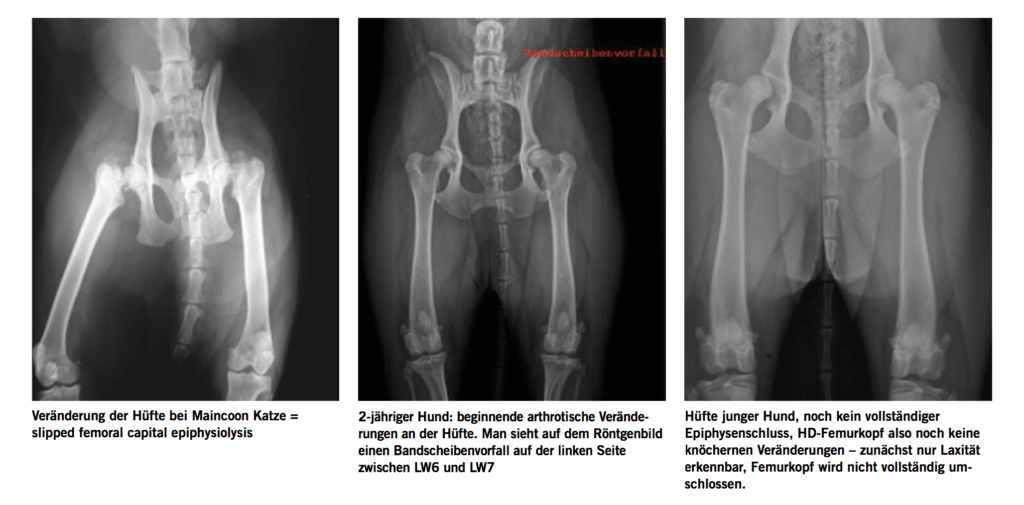

<h3>Hüftgelenksdysplasie (HD)</h3>

<p><a href="https://www.rogalla-rummel.de/wp-content/uploads/2018/12/spondylose_03.png"><img loading="lazy" class="img-responsive alignleft wp-image-6167 size-large" src="https://www.rogalla-rummel.de/wp-content/uploads/2018/12/spondylose_03-1024x424.png" alt="" width="1024" height="424" srcset="https://www.rogalla-rummel.de/wp-content/uploads/2018/12/spondylose_03-1024x424.png 1024w, https://www.rogalla-rummel.de/wp-content/uploads/2018/12/spondylose_03-300x124.png 300w, https://www.rogalla-rummel.de/wp-content/uploads/2018/12/spondylose_03-768x318.png 768w, https://www.rogalla-rummel.de/wp-content/uploads/2018/12/spondylose_03.png 2026w" sizes="(max-width: 1024px) 100vw, 1024px" /></a>Die HD gehört zu den häufigsten orthopädischen Erkrankungen bei Hund und Katze, klinische Bewegungsstörungen treten in der Regel erst im fortgeschrittenem Alter auf, obwohl die HD genetisch vorbestimmt ist. Allerdings können optimale Haltungs- und Ernährungsbedingungen die Arthroseentwicklung beeinflussen.<br />

Bei der HD liegt eine ausgeprägte Laxität der Hüfte vor: Die minder ausgeprägte Pfanne hält den Femurkopf nicht in Position und erlaubt ihm im schlimmsten Fall nach dorsal zu luxieren. Jeder Schritt belastet das Gelenk unphysiologisch, sodass sich mit der Zeit eine schwere Arthrose entwickelt. Die Diagnose HD wird im ersten Lebensjahr mittels Röntgen festgestellt. Es gibt schwere Fälle der HD, bei denen schon der junge Hund vor Vollendung des ersten Lebensjahres episodisch Lahmheit zeigt, bzw. schwer aufsteht, widerwillig läuft und Treppen vermeidet. Statt Galopp zeigt der Hund das sog. Bunny hopping: beide Hinterläufe werden im Rennen gleichzeitig vorgeführt. Auffällig ist bei allen Hunden mit zunehmendem Alter die Gewichtsverlagerung auf die Vorhand und der kurzgreifende Schritt der Hinterhand. Zusätzlich ist der Hüftschwung stark ausgeprägt. Die Entlastung der Hinterhand führt zusätzlich zur Muskelatrophie der Oberschenkelmuskulatur. Die Hunde zeigen einen breit ausgeprägten Brustkorb und eine schmale Hinterhand. Je nach Schweregrad der Arthrose zeigen sich die ersten Beschwerden ab dem 5. Lebensjahr.<br />